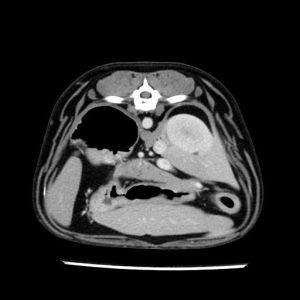

La lesione focale epatica , la ceus,la Tac e il chirurgo .